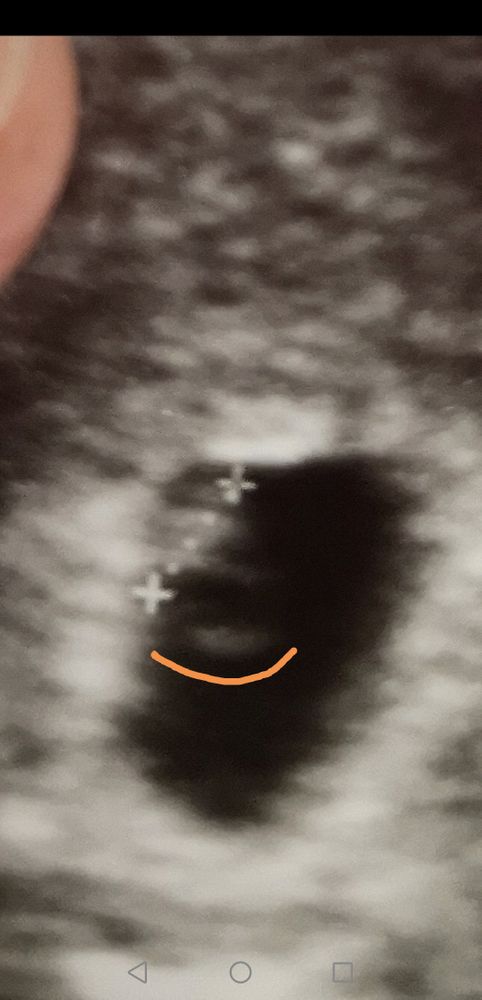

Мне кажется какие б близнецы небыли узи покажет два мешочка а не один

Узи показывает двойню хорошо, у вас один 90/100% Изображение

Karmilla, у вас ди ди на фото, а автор про моно спрашивает :)